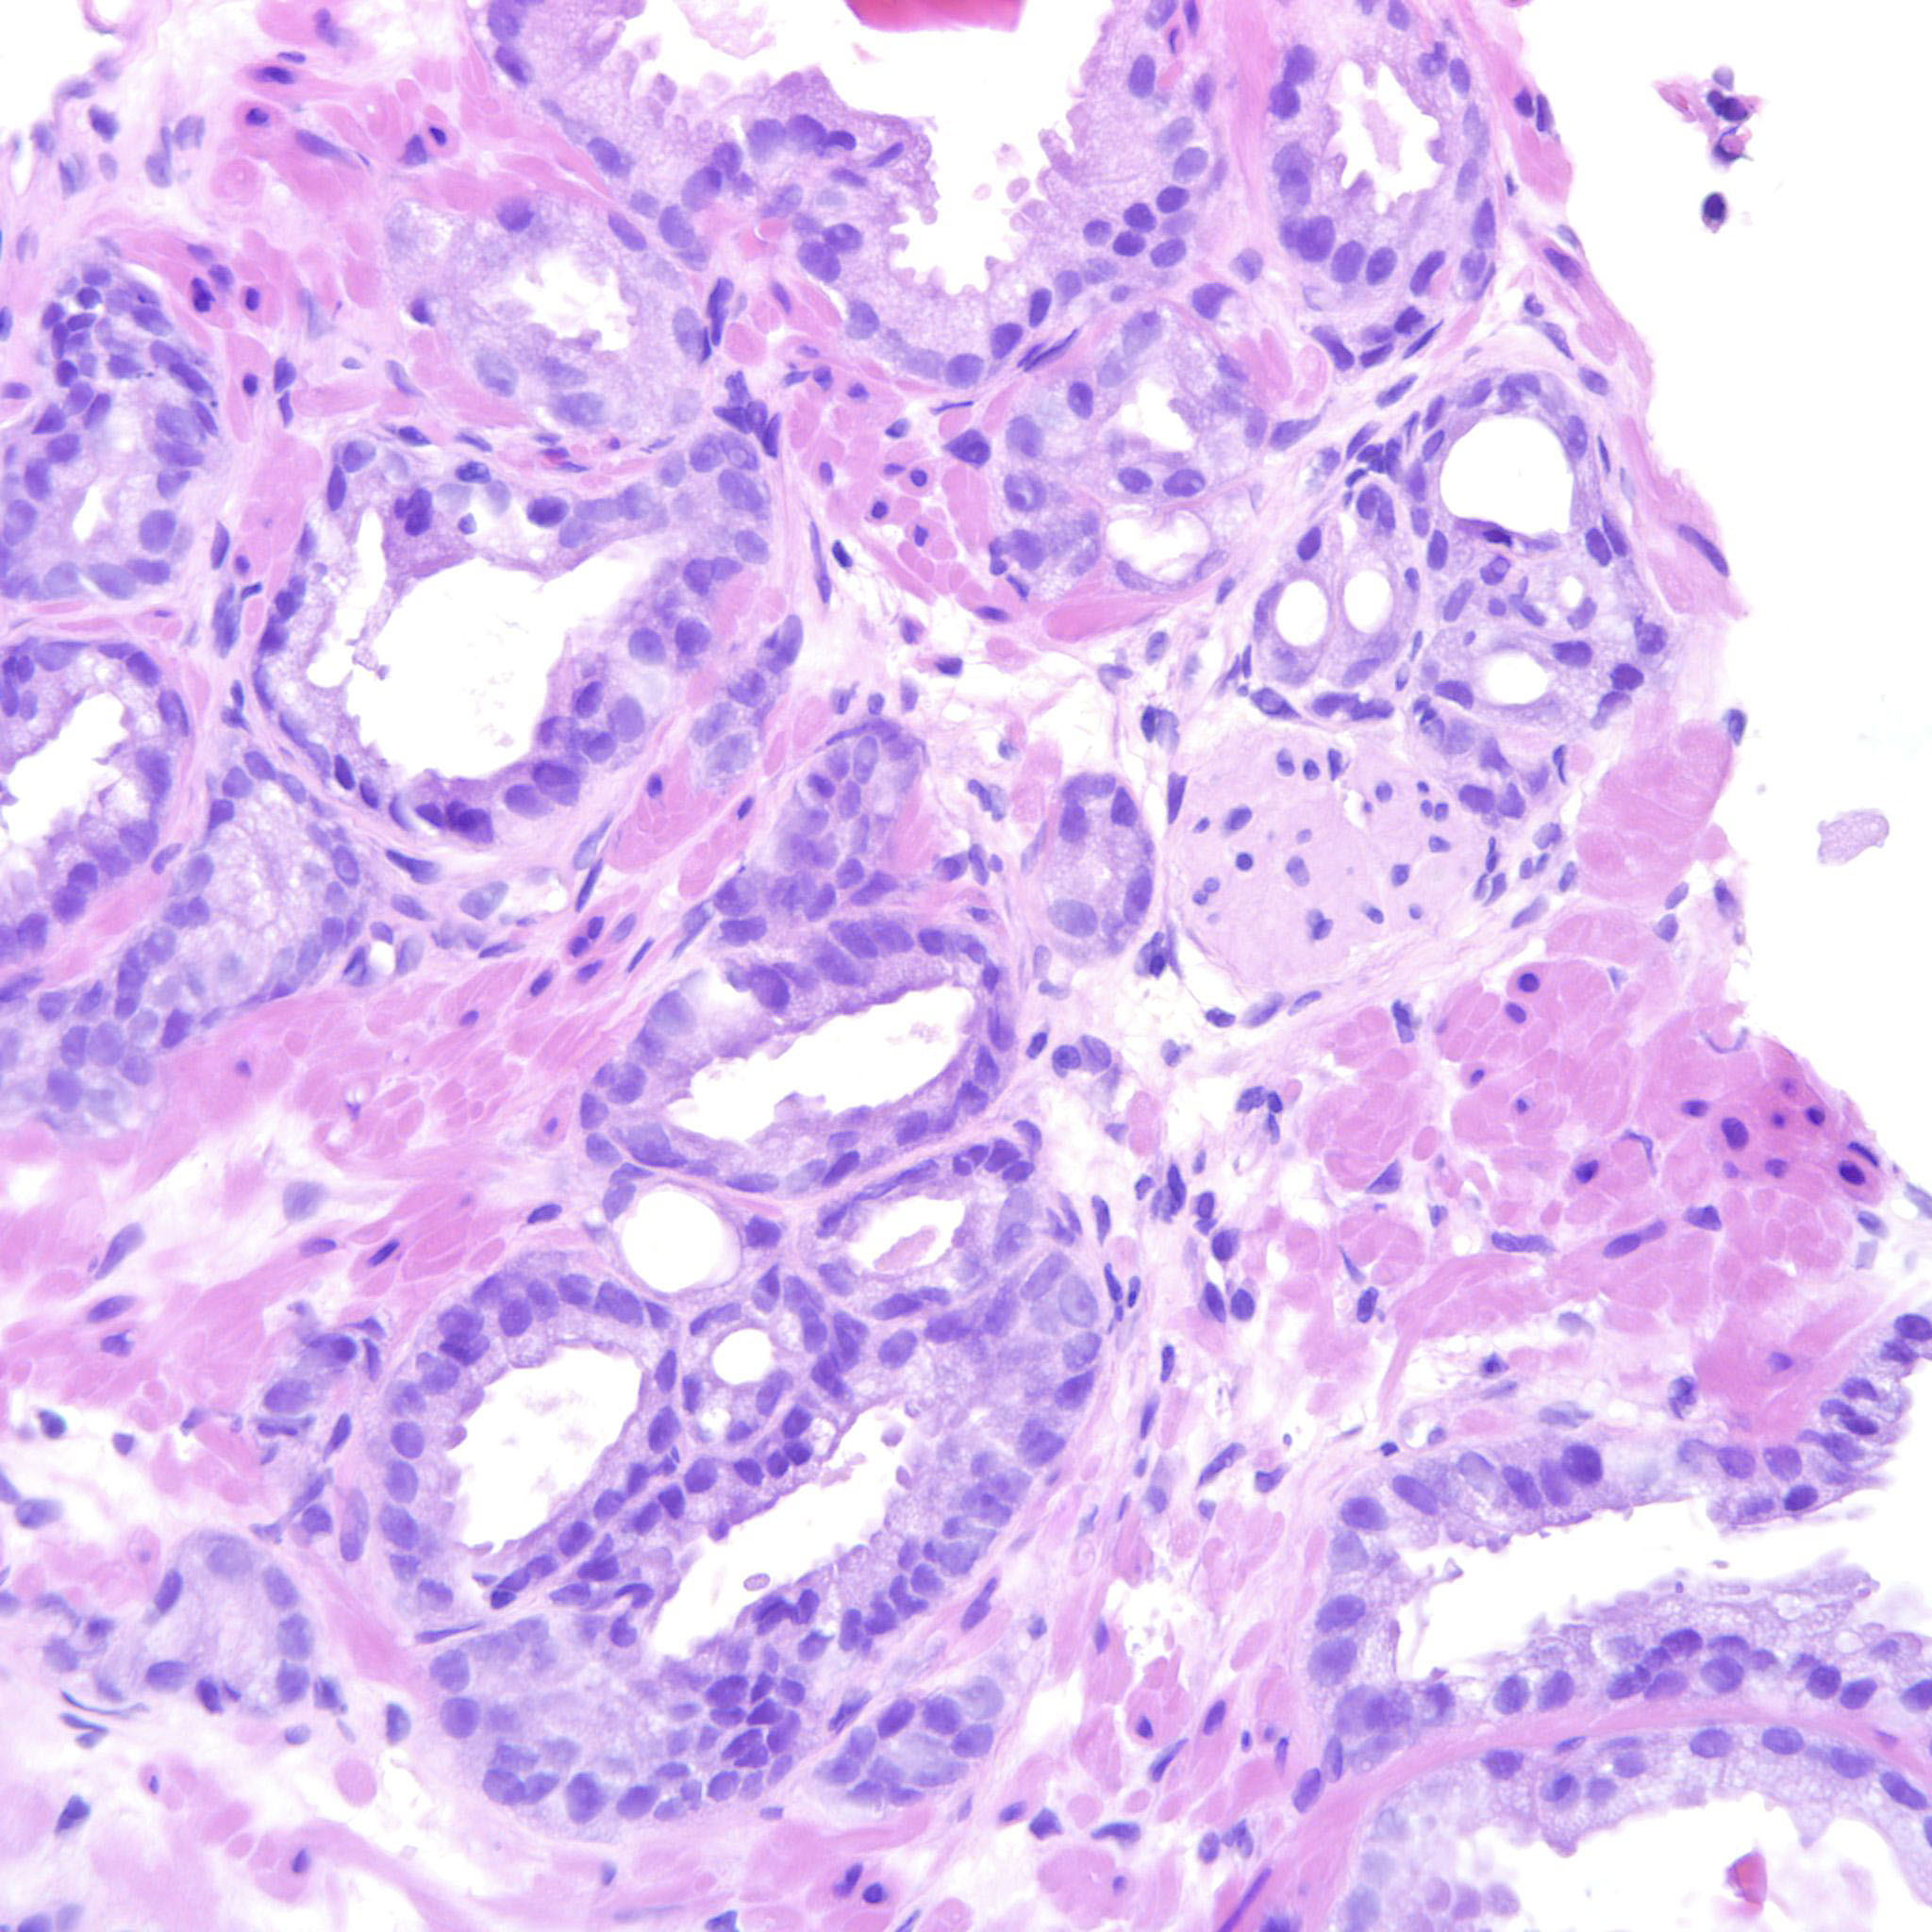

Consensus grade: GS 3+3=6 (ISUP 1)

3+3=6 with an occasional seemingly fused gland that may be a tangential cut.